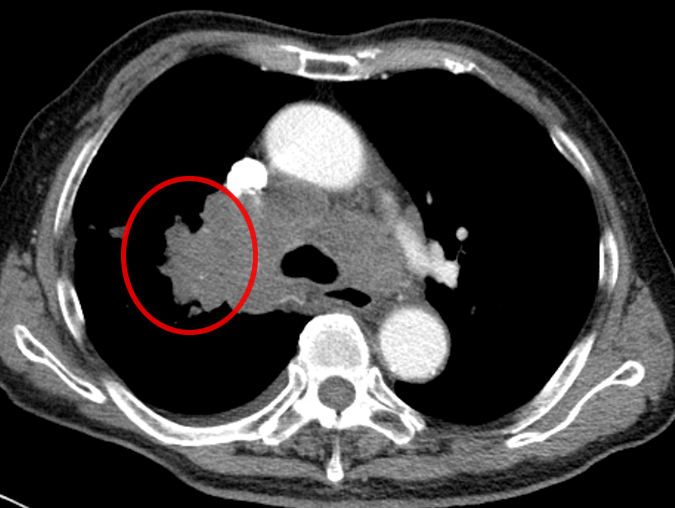

还有另一位患者,肺部结节只有 15mm,还合并了空洞,医生同样通过 CT 引导精准定位,成功完成经皮肺穿刺取到病理组织,最终诊断为 “腺癌”(免疫组化提示 CK7、TIF-1、NapsinA 阳性,排除其他类型肿瘤)。

什么是 CT 引导下经皮肺穿刺?

它就像一位精准定位的 “远程射手”:在 CT 的 “透视眼” 帮助下,医生能清晰看到肺部病变的位置、大小,以及周围的血管、气管等结构;随后用一根细针,从胸壁皮肤轻轻穿刺进入肺部,直达病变部位,抽取少量组织送检。

这种方式尤其适合深部或微小病灶—— 比如位置藏得深、体积小到 1cm 左右的病灶,CT 引导几乎是实现精准穿刺的唯一选择,能帮医生在不 “大动干戈” 的情况下明确肿瘤身份。